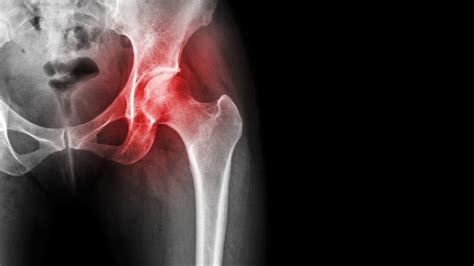

Living with chronic joint pain can be a debilitating experience, but when that pain originates deep within the hip, it often points toward a complex condition known as Avascular Necrosis (AVN). Often referred to in medical circles as osteonecrosis, Avn disease hip occurs when the blood supply to the ball portion of the hip joint is compromised. Because bone is living tissue that requires a constant flow of oxygenated blood to remain healthy and regenerate, this interruption causes the bone cells to die. Over time, if left untreated, the structural integrity of the femoral head weakens, leading to the collapse of the bone and severe, life-altering arthritis.

The progression of Avn disease hip is typically silent in its initial stages. In the early phases, patients may experience little to no discomfort as the bone cells begin to starve. However, as the bone weakens, the surface cartilage loses its structural support and begins to cave in. Understanding why this blood flow stops is critical for early diagnosis.

Stage III The "crescent sign" appears, indicating subchondral collapse. Constant ache, limited range of motion.

Stage IV Degenerative changes and joint surface destruction. Severe pain and significant mobility loss.